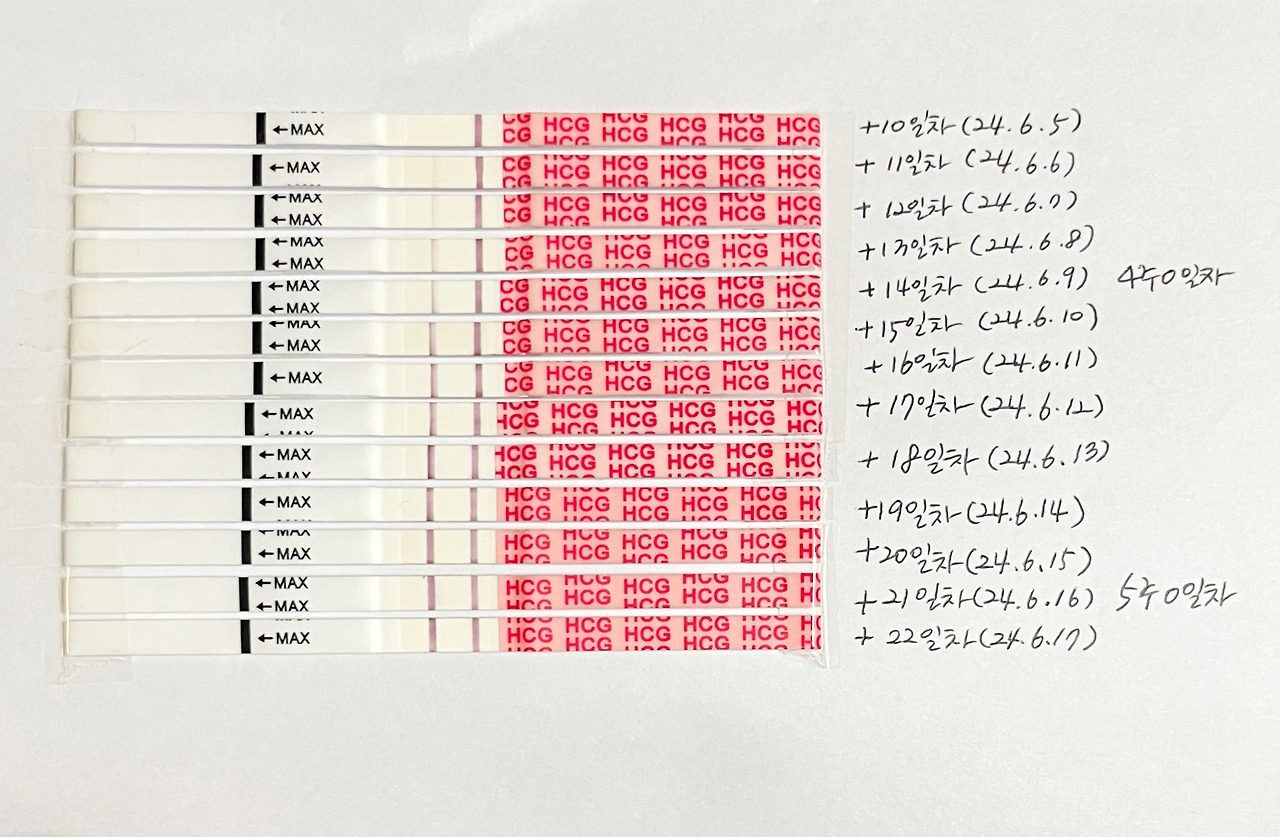

그렇게 나는 매일 테스트 하면서 테스트기가 조금씩 진해지는 것을 보며 아침을 활기차게 시작할 수 있었다.

배란 22일차, 임신 5주 1일차 예정인 날로 아기집을 볼 가능성이 있는 5주차 초에 병원 진료를 잡았다.

매일 아침 테스트 하는게 임신 초기 때 낙이자 하루의 큰 일과였다.

그렇게 하루하루 길었던 임신 초기...

배란 22일차 병원 가는 날 아침에도 기분 좋게 테스트를 하고...!

23일차, 25일차에도 임테기를 해보았는데

사실 이제 임테기는 더 의미 없는 것 같아서 25일차를 마지막으로 했다.ㅎㅎ

배란 11일차, 25일차 임테기 비교